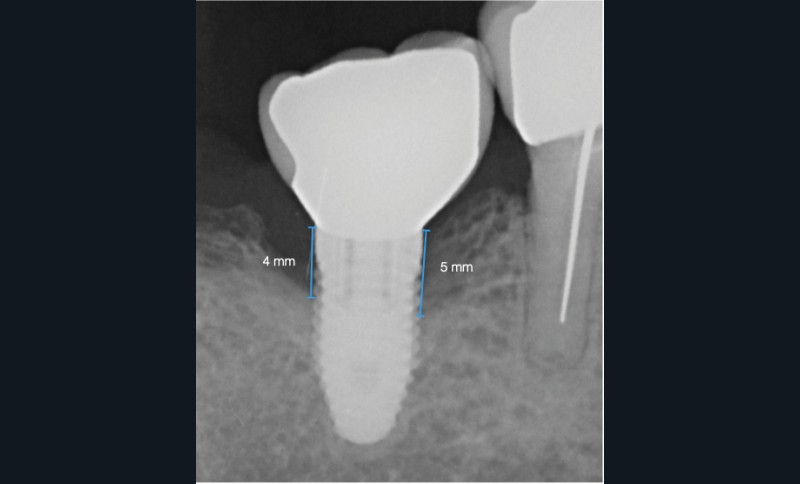

Conclusions

Dans les cas de traitement de péri-implantite, un suivi d’un an est considéré comme un suivi court. Néanmoins, le cas présent est stable après un an et ne présente aucun signe de récidive. Des contrôles supplémentaires sont nécessaires.